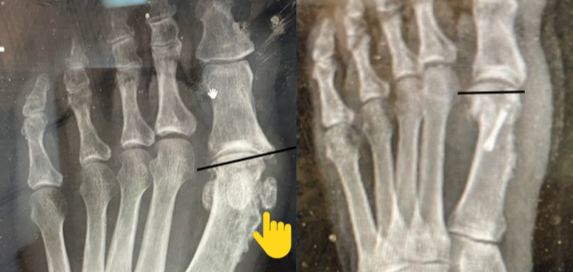

Blog's main page The images may appear relatively straightforward on initial inspection. However, some crucial points can allow revisional, or any, bunion surgery to have a greater chance of long-term [...]